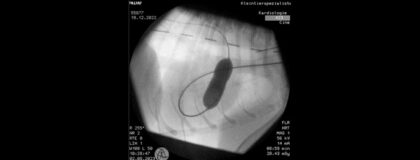

Referent: Peter Zufall: Tierarzt, Resident ECVIM-CA (Cardiology), Zusatzbezeichnung Kardiologie beim Klein- und Heimtier, GPCert Small Animal Ultrasound (ISVPS), Mitglied im Collegium Cardiologicum e.V., Kleintierspezialisten Berlin

Nachdem wir uns in einem vorherigen vetinar bereits mit der Volumenbelastung beschäftigt haben, soll dieses mal die Druckbelastung im Fokus stehen. Auch hier stellen wir uns die Frage nach Pathologie, Prädisposition, Klinik, Diagnostik, Therapie, wobei wir auch über interventionelle Behandlungsmöglichkeiten sprechen werden.